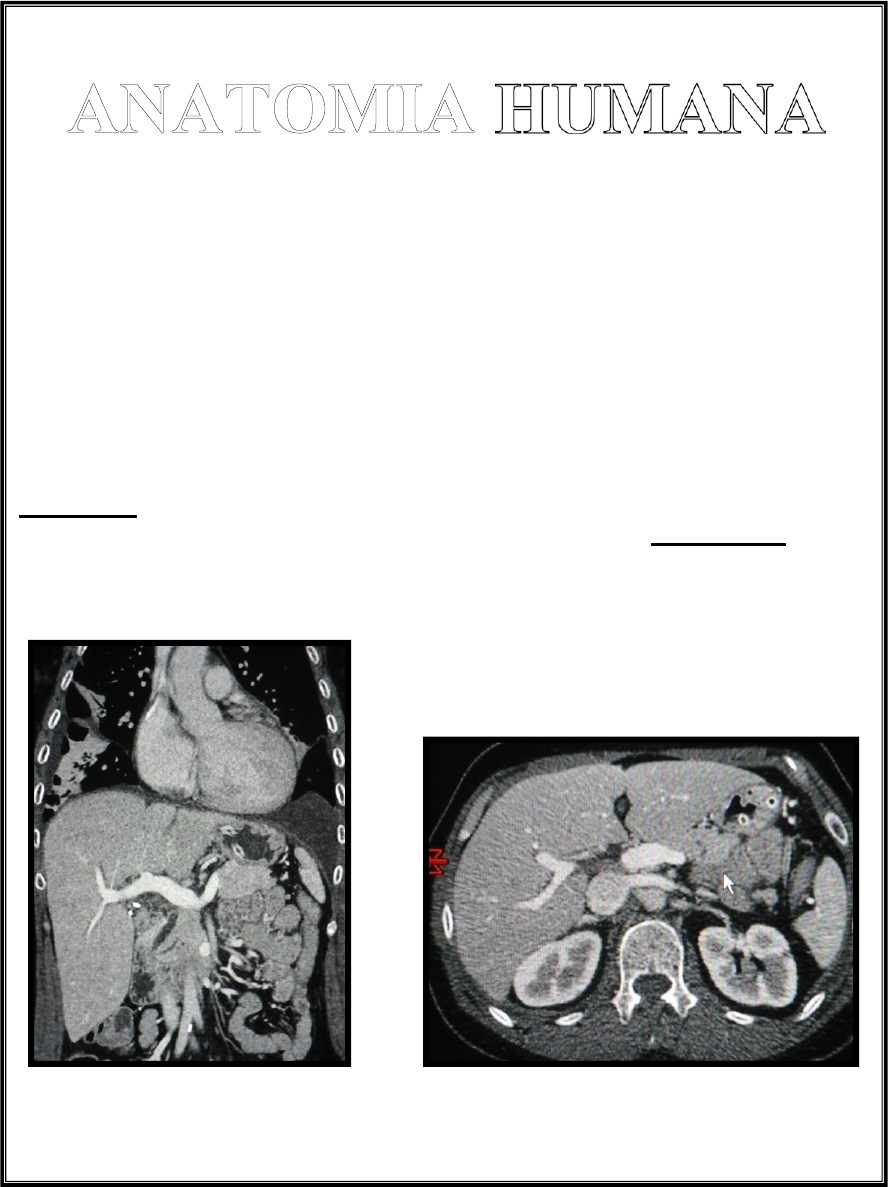

Aparato Urinario

El sector urinario comprende los riñones, uréteres, vejiga y la uretra.

Los riñones son dos y están ubicados en la región retroperitoneal lateral, presentan una

zona periférica denominada corteza y una zona central denominada médula, a partir de

donde se forman los cálices menores y mayores, la pelvis renal, el uréter (este último recorre

en forma descendente el retroperitoneo a los costados de la columna vertebral hasta

encontrar la vejiga).